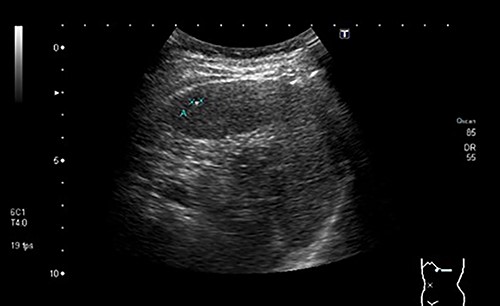

During a screening imaging examination of her liver disease, a lesion suspected of malignancy was detected. The ultrasound disclosed a hypoechoic nodule, vaguely heterogeneous, located in segment VII, subcapsular, and with ~22 mm in diameter (Fig. 1). Liver blood tests and serum alpha-fetoprotein level were normal. For better characterization, a CT scan was performed. The CT showed, in addition to signs of chronic liver disease, the presence of a solid subcapsular nodule of segment VII, measuring 23 mm, with hypervascular behavior in the arterial phase (Fig. 2) and washout in late venous phase (Fig. 3).

Ultrasound showing a hypoechoic nodule, vaguely heterogeneous, located in segment VII, subcapsular, and with ~22 mm in diameter.